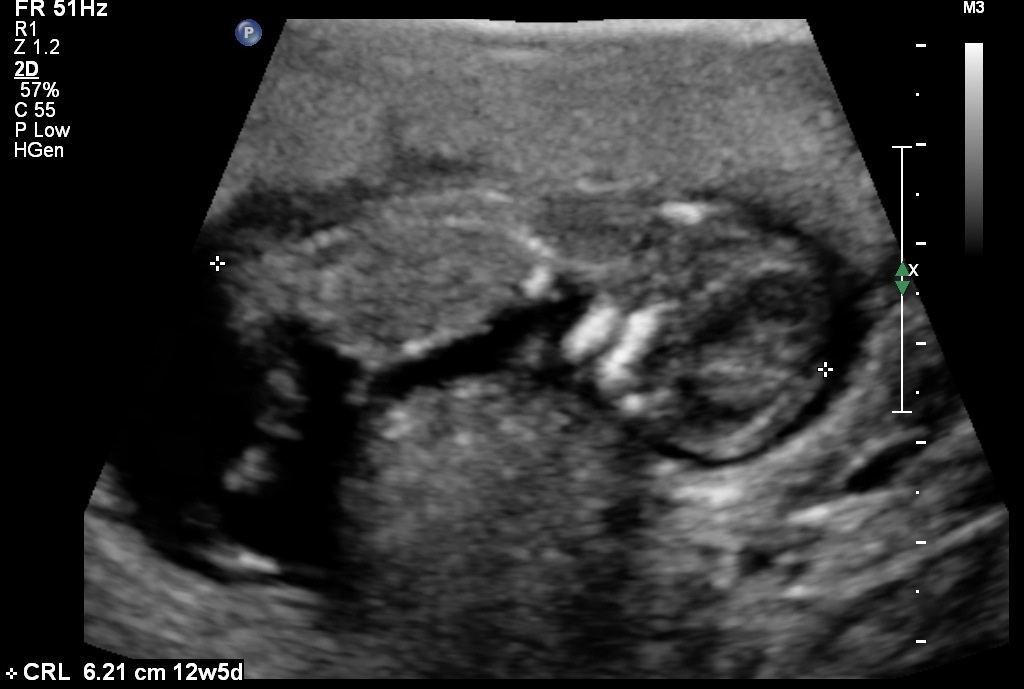

I know it is early and this isn't a great pic, but any thoughts on gender? I was 12 weeks, 1 day.

Yeah I wasn't given any good profile shots.:-/ Here's what I have...Attachment 12408Attachment 12409Attachment 12410

Sure let me try...Attachment 12423Attachment 12424Attachment 12425Attachment 12426